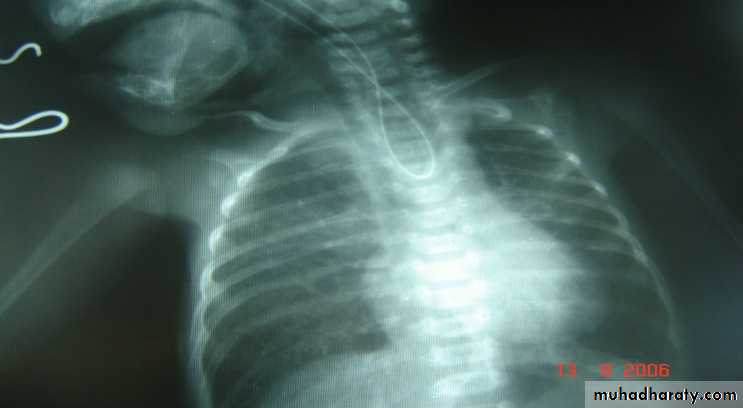

1-x-ray of the cheast &abdomen provides informations about the followings:

a-coiling of NGT and level of obstruction.

b-prescence of air in the stomach which indicates fistula.

c- states of the lungs.

d-vertebral &ribs anomalies.

e- evidence of right aortic arche.